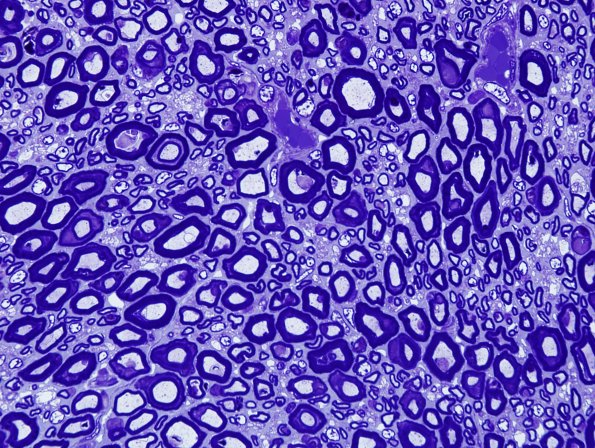

Washington University Experience | PERIPHERAL NEUROPATHY | 8 ACUTE MOTOR AXONAL NEUROPATTHY (AMAN) | 1A5 AMAN (Case 1) Plastic 12.jpg

An additional example of macrophage nuclei within the myelin sheath adjacent to the axon. (Plastic sections)